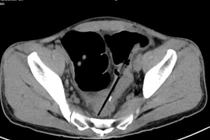

(khoahocdoisong.vn) - Khoảng 1kg dị vật kim loại như đinh, thìa, bấm móng tay, lưỡi dao, thỏi sắt, móc đồ... đã được lấy ra khỏi một bệnh nhân nam (27 tuổi, Tân Uyên, Bình Dương). Đây là trường hợp hiếm gặp, có dấu hiệu của hội chứng pica.

Nguyên nhân trong ổ bụng bệnh nhân có nhiều dị vật là do người bệnh được chẩn đoán mắc hội chứng Pica, hay còn gọi là hội chứng thích ăn các đồ vật không phải thức ăn.

Trung tâm Phẫu thuật tiêu hóa - Bệnh viện Bạch Mai vừa phẫu thuật một trường hợp người bệnh nuốt nhiều dị vật gây biến chứng thủng đại tràng. Người bệnh được chẩn đoán mắc hội chứng Pica (hội chứng thích ăn các đồ vật không phải thức ăn).